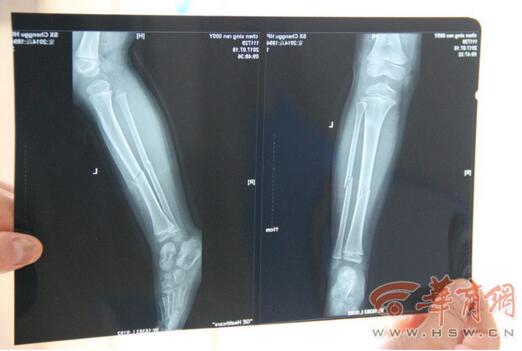

記者看到,明明除了左腿骨折外,鼻子上一塊傷痕已經結痂,腿上和胳膊上也留下了傷痕。明明精神狀態看起來挺好,一直玩著玩具,似乎全然忘記了疼痛。“叔叔騎著摩托車,說帶我去找媽媽,然后去看病,最后他把我往垃圾箱里塞,又把我放在了垃圾堆里就走了。”明明說。

明明的主治醫生說,明明左小腿粉碎性骨折,不排除會留下后遺癥,“以后可能會走路一高一低”。